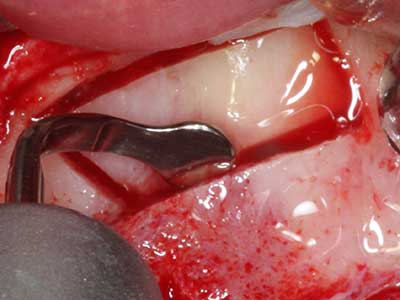

Indication: Preparation near nerves

When surgical procedures are performed on bone in the immediate vicinity of sensitive structures such as blood vessels or nerves, rotary instruments pose a significant risk of iatrogenic injury. Piezoelectric devices can be helpful for preparation of bone covers and removal of hard tissue close to nerves, particularly for exposure of nerves after iatrogenic injury but also during nerve lateralization for resective and reconstructive procedures or implant placement (Fig. 17-20). Light contact between the piezotip and the nerve does not generally result in damage but proceeding incautiously with saw-like motions or attachments where a residual bone substrate remains may cause temporary or even permanent nerve damage. However, the risk of damage is considered to be substantially lower than when using saws or milling instruments (Pereira, Gealh et al. 2014).